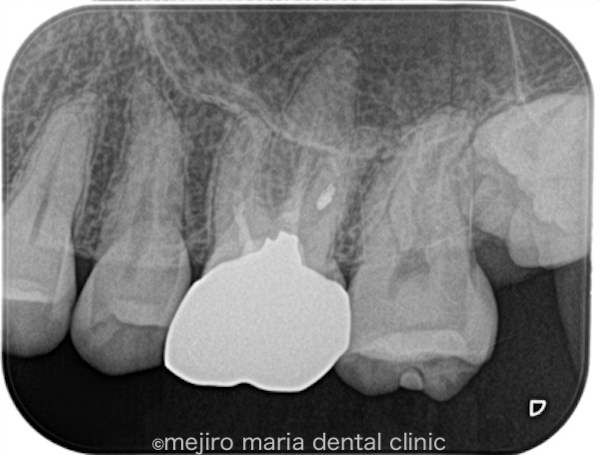

左上6番(上顎左側第2大臼歯)は既に根管治療が施されており、根尖性歯周炎は根尖に確認されないものの、以前の治療の質は良い状態ではない(質が低い)ことが予想できます。根管治療の質を高める意味合いで再根管治療をご提案させていただきました。